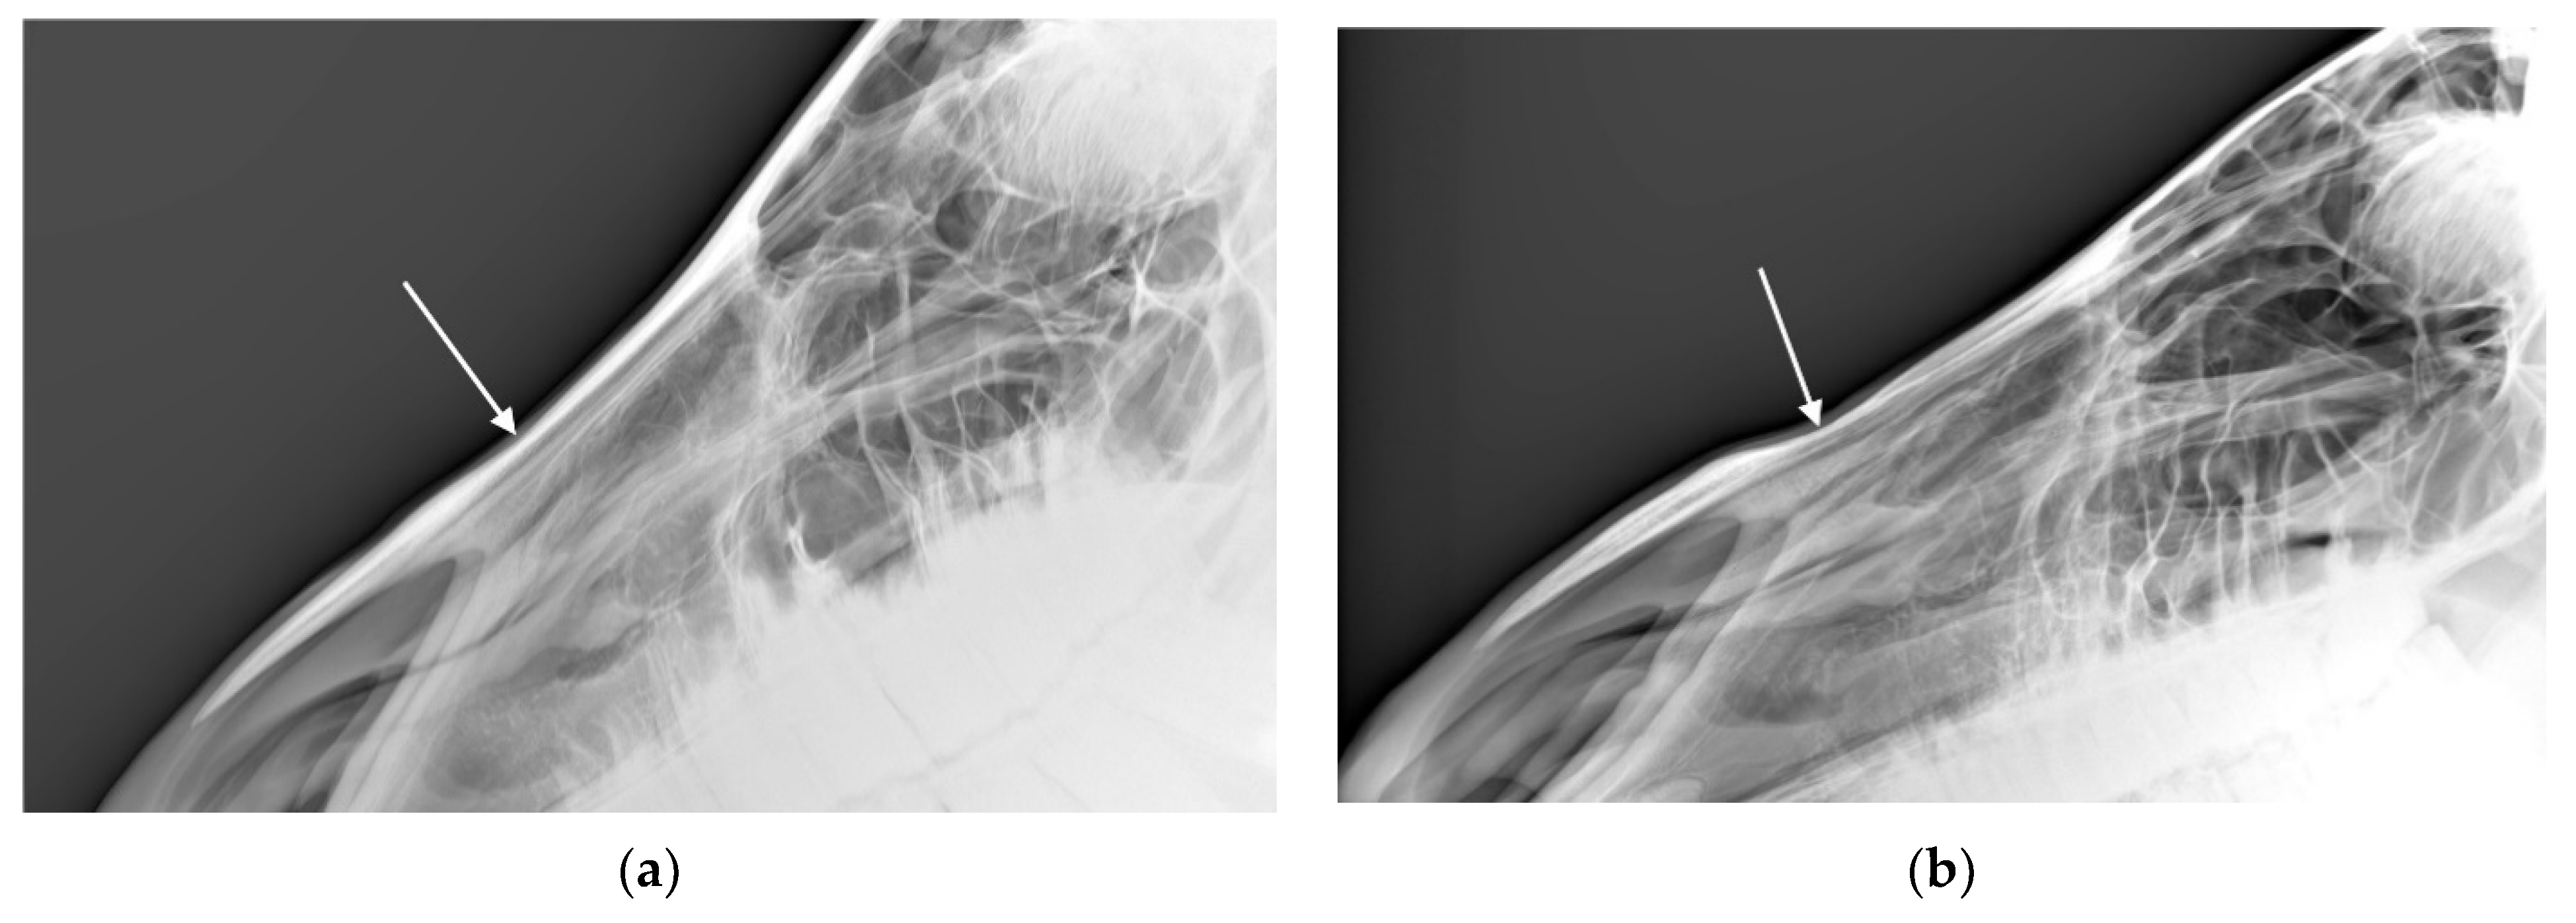

For the 54 horses where the radiologists agreed there was at least one radiographic nasal bone change, the radiologists agreed about the presence or absence of bone deposition in n = 47 (87%; see Figure 4), the presence or absence of bone thinning in n = 45 (83%; see Figure 5), the presence or absence of loss of bone homogeneity in n = 43 (80%), and the presence or absence of soft tissue swelling in n = 49 (91%).

(1) Bone Deposition

Bone deposition in the nasal bone region was noted on the radiographs of between 6.9% (n = 10) and 8.3% (n = 12) of the 144 horses. For most of these horses (n = 8–10), the noted change was mild. Marked changes were reported in no horses. Agreement was moderately good with a percentage agreement = 89.6% and a square weighted Cohen’s kappa = 0.622 (z = 7.47, p < 0.001)

Figure 4. Radiographs showing the nasal bones of a horse in which radiologists (n = 2) agreed there was bone deposition that was: (a) typical of affected horses and (b) moderate.